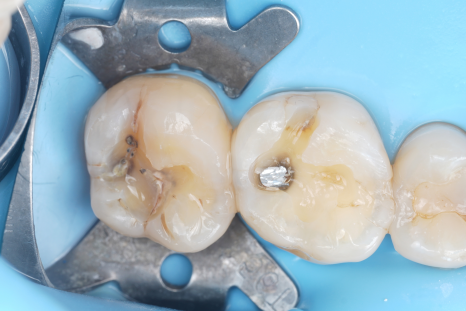

큐레이 전, 후

그럼에도 제가 큐레이를 고집하는 이유는 아주 단순해요. 충치와 건강한 치질의 경계를 정확하게 보여주기 때문입니다.

충치는 겉과 속이 다른 경우가 많아요.

치과보존과

겉으로 보기에는 작은 점처럼 보여도 안쪽에서는 더 넓게 진행되어 있는 경우도 꽤 많아요.

문제는 눈으로만 진료하면 이 경계를 정확히 판단하기 어렵다는 거예요.

그래서 치료를 하다 보면 이런 일이 생길 수 있어요. 충치가 아닌 부분까지 같이 삭제되거나 혹은 반대로 충치가 남아버리는 경우도 생기죠.

하지만 큐레이를 사용하면 충치가 있는 부분과 건강한 치질의 경계가 비교적 명확하게 드러나요. 말 그대로 '어디까지 진료해야 하는지'를 보여주는 장비라고 생각하시면 돼요^^